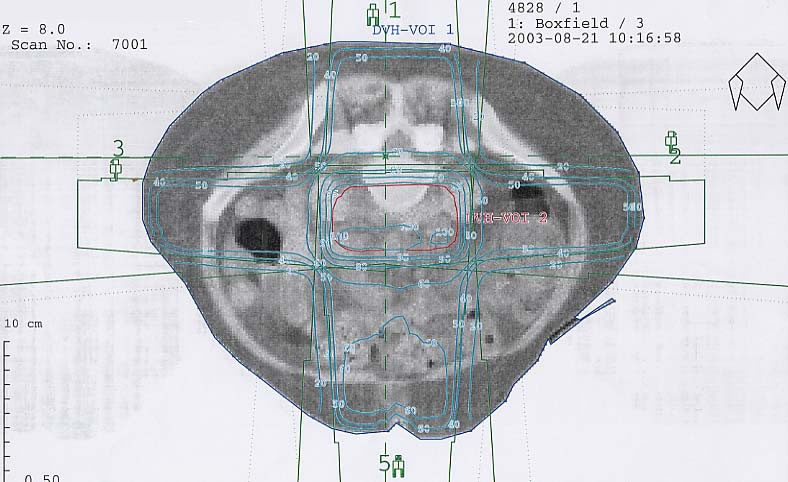

Gynäkologische Tumore des Beckens: Bestrahlungsplan

Einführung aktuelle Bilder - Einführung Bestrahlungspläne - Einführung Demonstration